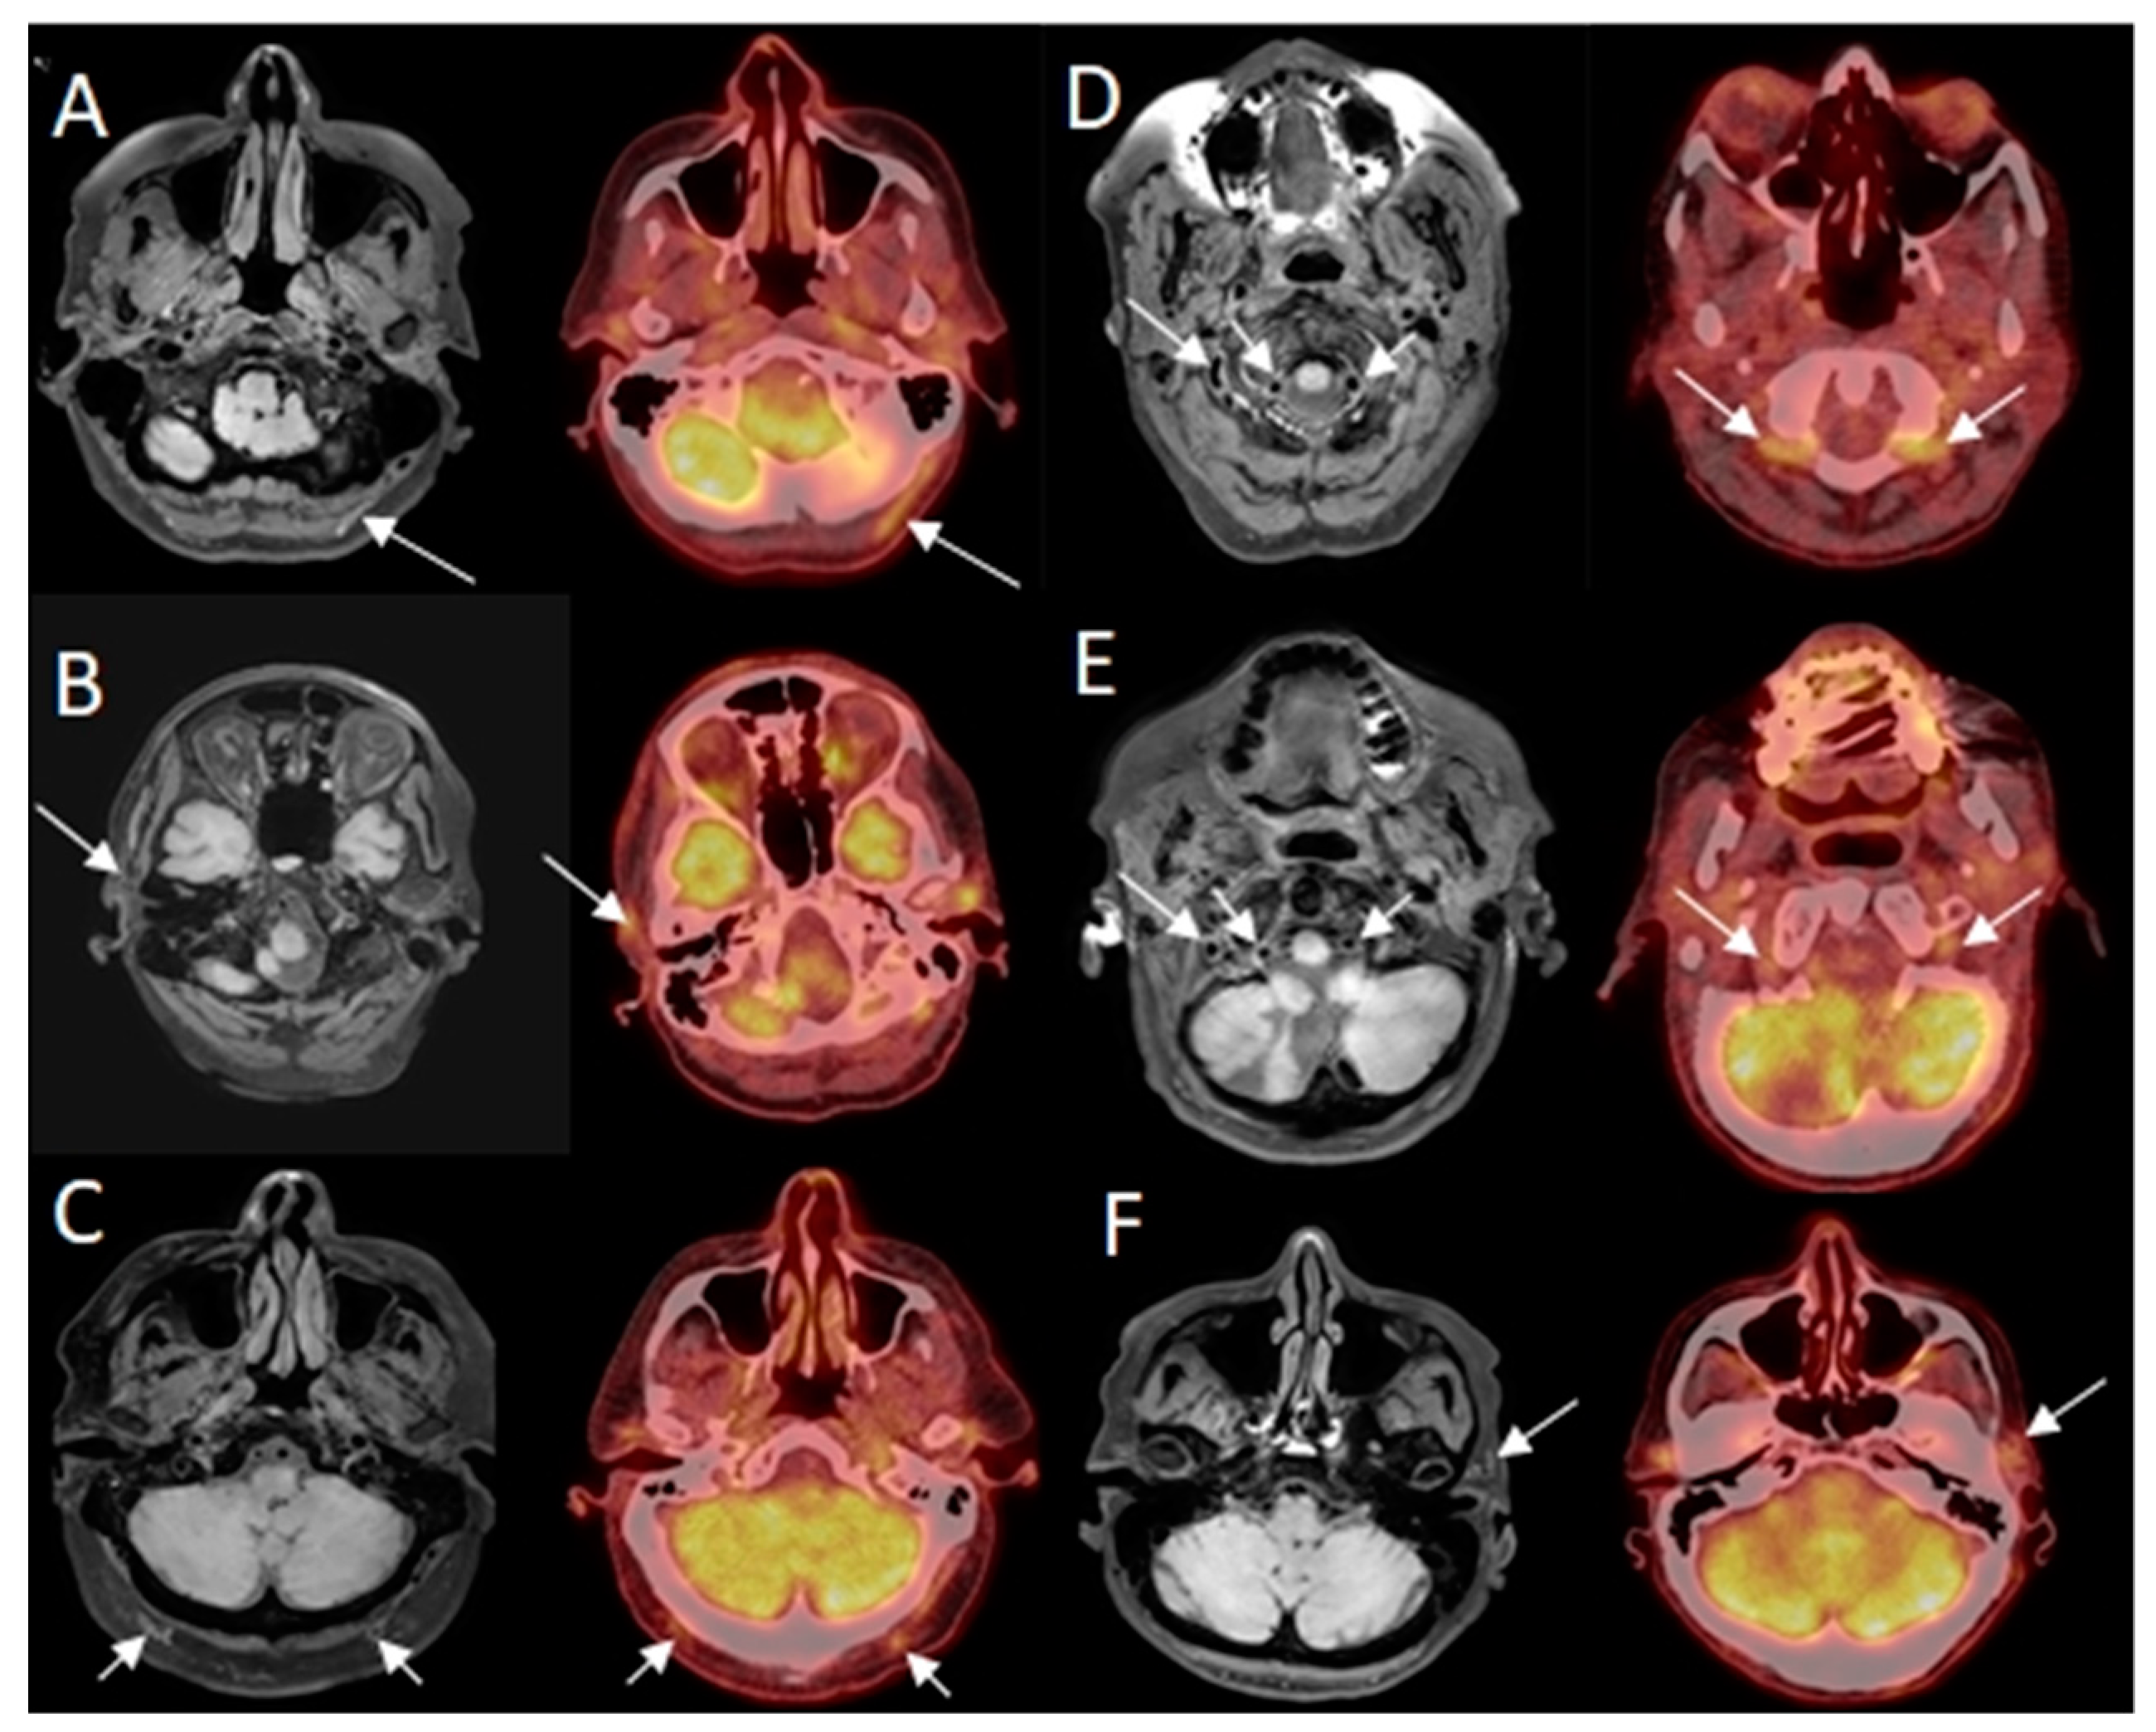

Eight out of ten patients were diagnosed with GCA. Of these eight patients, all eight were correctly identified as positive, independently, by both neuroradiologists reading the BB-MRI images. It was not possible to discriminate whether the inflammation was localized in the periadventitial tissue or in the adventitia. These patients were also correctly diagnosed from 2-[18F]FDG PET/CT and US examinations. Regarding the TAB results of the eight GCA-positive patients, one was a false negative, one renounced having the TAB performed, and the remaining six were positive. The patient whose TAB was deemed false negative had the final diagnosis of GCA based on clinical examination after six months, with results including fulfillment of three out of five ACR 1990 GCA classification criteria, elevated CRP, positive US, and positive 2-[18F]FDG PET/CT. No ophthalmological consequences of GCA were revealed in the patient by the neuroophthalmological examination. Two out of ten patients were diagnosed as GCA-negative, and were correctly identified as GCA negative by both neuroradiologists reading the BB-MRI images. Both patients were confirmed to be GCA negative by 2-[18F]FDG PET/CT, US, and TAB. There were no false negative or false positive 2-[18F]FDG PET/CT or US scans when using the final diagnosis after six months as the reference test. Four out of five participants in the control group were negative on the BB MRI, with one false positive. The 2-[18F]FDG PET/CT was GCA-negative, as per inclusion criterion. Compared with 2-[18F]FDG PET/CT as the reference test, BB MRI had a sensitivity, specificity, PPV, and NPV of 100.0% (95% CI: 63.1–100.0%), 85.7% (95% CI: 42.1–99.6%), 88.9% (95% CI: 68.4–100.0%), and 100.0% (95% CI: 100.0–100.0%), respectively, for diagnosing GCA. Due to motion artefacts, two BB MRI scans were of a poorer quality. This did not affect the diagnostic accuracy of BB MRI compared to the other imaging modalities or TAB. Hence, all 15 BB MRI scans were diagnostic. A head-to-head comparison of affected arteries on US, 2-[18F]FDG PET/CT and BB MRI showed some discrepancy. Generally, more arteries were evaluated as inflamed on US and 2-[18F]FDG PET/CT than on BB MRI (data not shown). In 14 of the 15 BB MRI scans, the two neuroradiologists made the same diagnosis. In the last case, a consensus diagnosis was made, favoring GCA, which was correct. Examples of imaging results of 2-[18F]FDG PET/CT and BB MRI are shown in Figure 1 and Figure 2.

Examples of findings of giant cell arteritis (GCA) on high-resolution T1-weighted 3D black blood without contrast enhancement Magnetic Resonance Imaging (BB MRI) compared to 2-deoxy-2-[18F]fluoro-D-glucose positron emission tomography/low-dose computed tomography (2-[18F]FDG PET/CT). Hyperintense signal in/related to the artery wall on axial BB MRI (arrows) and increased FDG uptake in arteries on axial fused PET/CT (arrows). Note: BB MRI and 2-[18F]FDG PET/CT images are not perfectly aligned, as best visualization of the same affected artery is dependent on head position. Not all affected arteries are marked on 2-[18F]FDG PET/CT. (A) patient with GCA affecting the left occipital artery; (B) patient with GCA affecting the right temporal artery; (C) patient with GCA affecting the right and left occipital artery; (D) patient with GCA affecting the right and left vertebral artery; (E) patient with GCA affecting the right and left vertebral artery; (F) patient with GCA affecting the left temporal artery.

Figure 1 Cranial giant cell arteritis visualized on BB MRI and 2-[18F]FDG PET/CT.